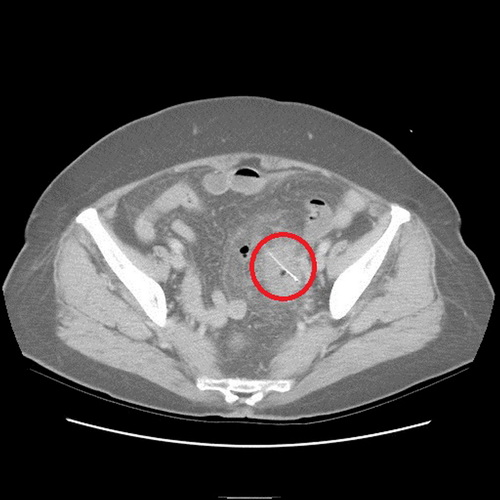

沒(méi)想到過(guò)了2天,老奶奶又來(lái)看診,醫(yī)師便為她安排住院檢查,經(jīng)計(jì)算機(jī)斷層檢查,發(fā)現(xiàn)老奶奶乙狀結(jié)腸部份竟然有根2.5公分的魚刺,且魚刺已經(jīng)穿破腸道,導(dǎo)致橫膈膜下方有氣體出現(xiàn),經(jīng)外科醫(yī)師協(xié)助開(kāi)刀,終于順利幫老奶奶解決腹部不適的問(wèn)題。